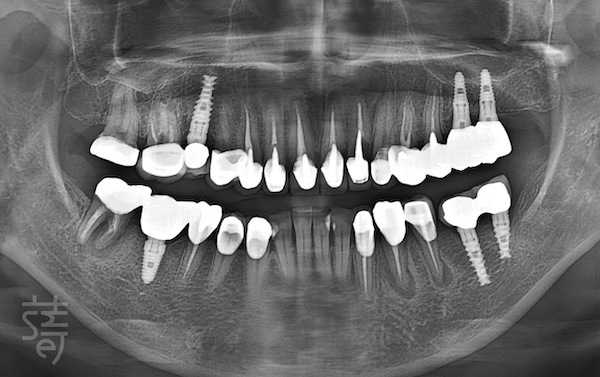

在江政倫院長的診斷下,張小姐的問題終於明朗。她早年缺牙未及時處理,對咬的牙齒慢慢「變長」,導致整體咬合面紊亂。

過去的治療多半只針對單顆牙問題,未從整體咬合角度評估,甚至直接在錯誤的咬合基礎上植牙,造成牙齒彼此干擾,問題當然接連出現。

更麻煩的是,前牙與後牙之間本有保護機制。當後牙支撐不穩,受力會轉移到前牙,久而久之,連前牙也磨損壞裂,全口出狀況。